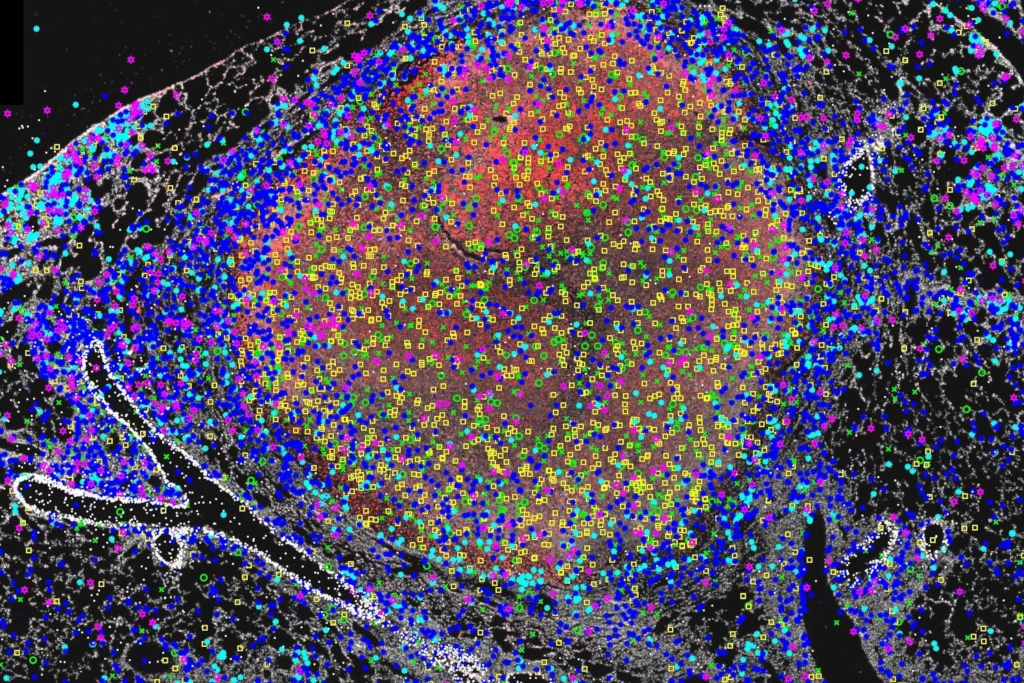

Not much is known about what happens inside the granulomas but in a recent study, researchers from SciLifeLab, Karolinska Institutet and the Boston University School of Medicine created a detailed map of the immune response inside the granulomas by using “In situ sequencing” – a technique used to identify active genes in tissue samples – of 34 immune markers in mouse tuberculosis.

The researchers could define central patterns for different granuloma types and how the immune system responds in close proximity to the bacteria. The findings were published in Nature Communications and can help speed up the design and evaluation of new vaccine candidates against Tuberculosis.

Photo: BA Carrow et al.